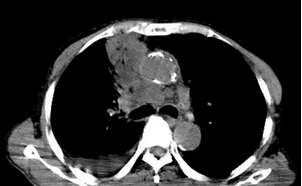

上圖是術(shù)后第三天CT增強(qiáng)掃描的圖片,雖然病灶的部位非常不好,靠近大血管、氣道,但可以看到腫瘤內(nèi)部絕大部分都被一次消融殺死,患者本人和遠(yuǎn)道趕來(lái)的家屬都非常滿意這個(gè)結(jié)果。